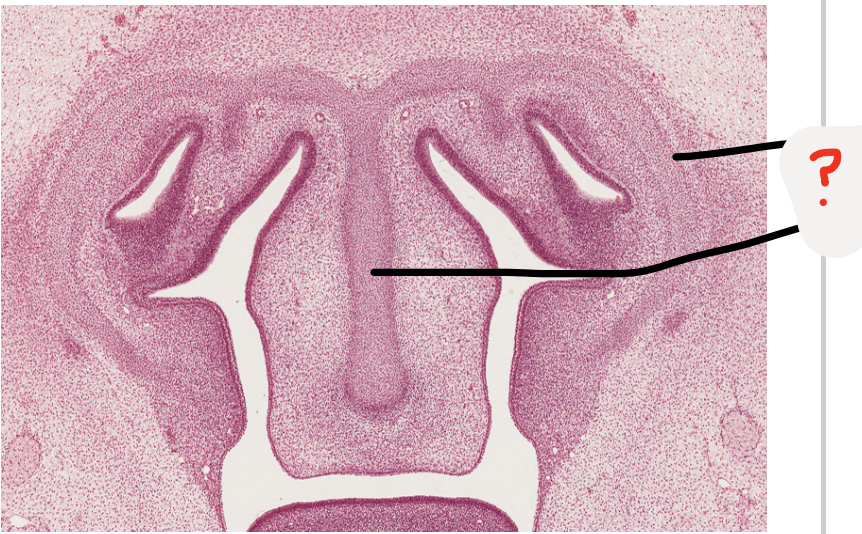

what is the line pointing at?

bone formation

what is this structure at the base of the nasal capsule?

developing vomer dark cells are osteoblasts making bone

Nasal capsule is made up of cartilage -> nasal septum is part of it

this will be the sulcus